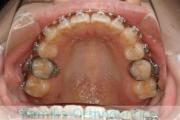

No.23V-478

- 叢生

- 30歳

- 男性

- 抜歯部位

- 上:

- 44済

- 下:

- 8558済

- 主な使用装置:

- FEA 022

- 治療にかかった費用:

- 76万円

右上の歯が重なっているところが邪魔になるとのことで矯正治療を始められた患者さんで、札幌から転院されました。当院で約1年半、15回程度の通院が必要でした。叢生(でこぼこ、凹凸、ガタガタ)が強く、後戻りのリスクが高いケースです。